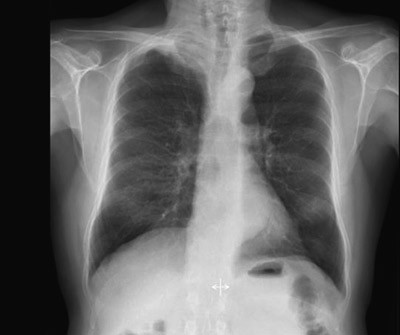

Røntgen thorax (fig 1) tatt rutinemessig ved innkomst viste en oppfylling i høyre lungetopp. CT collum/thorax/abdomen avdekket en ca. 6 cm stor svulst apikalt i høyre lunge (fig 2a, b). Det var ingen tegn til patologisk forstørrede lymfeknuter eller andre svulster. Bildene viste i tillegg emfysemforandringer og et stort abdominalt aortaaneurisme.

På grunn av beliggenheten kan disse svulstene være vanskelig å oppdage ved konvensjonell røntgenundersøkelse. Det ses ofte kun apikal pleurafortykkelse med asymmetri av lungetoppene. Fordi skuldersmerter er et av de mest typiske symptomene, blir mange initialt behandlet for antatte muskel-skjelett-plager, og symptomene kan vedvare i måneder før videre utredning igangsettes. Forsinket diagnose bidrar til at de fleste av disse svulstene oppdages i et avansert stadium – noe som har konsekvenser for overlevelsen (2). I et materiale fra Attar og medarbeidere var median overlevelse ved T3-sykdom 36,8 måneder, 6,4 måneder ved T4-sykdom (10).